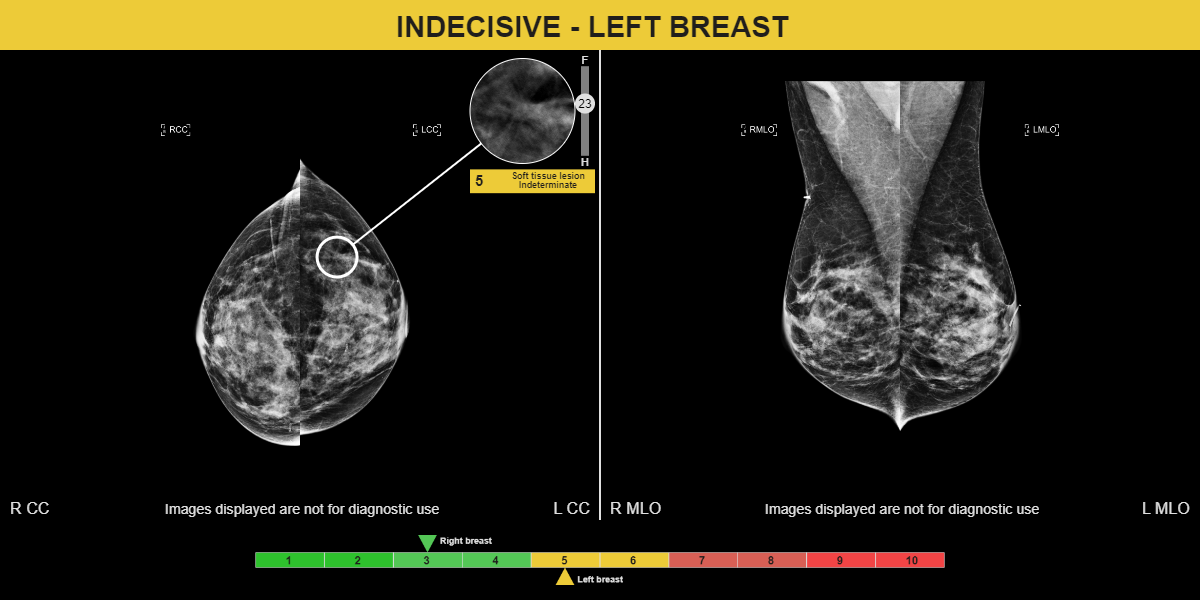

Architectural distortion in the upper outer left breast was detected in 2016 by the original reader. A prior exam dating in 2015 was included in the clinical study in which MammoScreen highlighted the cancer with a score of 5. Thirteen radiologists recalled this case utilizing MammoScreen; while only 9 radiologists recalled it when unassisted by MammoScreen .

Moreover, utilizing MammoScreen, the reading time for this case was reduced by 21% on average.